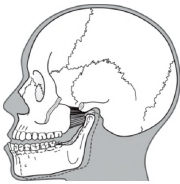

Os músculos da mastigação são compostos por

quatro pares de músculos.

Analise a figura abaixo:

OKESON, JP. Tratamento das desordens Temporomandibulares

e Oclusão

OKESON, JP. Tratamento das desordens Temporomandibulares

e Oclusão

A figura representa, respectivamente, o seguinte músculo e sua função correta:

OKESON, JP. Tratamento das desordens Temporomandibulares

e Oclusão

OKESON, JP. Tratamento das desordens Temporomandibulares

e Oclusão A figura representa, respectivamente, o seguinte músculo e sua função correta: